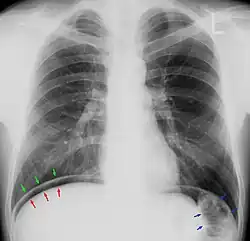

Pneumoperitoneum im Thoraxröntgenbild. Die freie „Luft“ ist zwischen dem Oberrand der Leber (rote Pfeile) und dem Zwerchfell (grüne Pfeile) zu erkennen. Die blauen Pfeile zeigen auf den gasgefüllten Dickdarm (normal). -